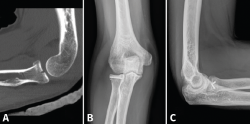

Las fracturas que afecten a menos de un tercio de la cabeza radial y que no produzcan bloqueo de la articulación podrían tratarse de igual modo que las de tipo I con buenos resultados a largo plazo. Inestabilidad y desplazamiento no son sinónimos. Incluso con un desplazamiento de más de 2 mm o con más de un fragmento, hay fracturas que siguen siendo estables gracias a que las estructuras periósticas están preservadas; por tanto, no son indicación absoluta de tratamiento quirúrgico (Figura 2)(11,12).

Figura 2. Ejemplo de fractura de Mason II tratada de forma conservadora. A: proyección anteroposterior (AP) aguda; B y C: AP y lateral a los 6 meses.

- Reducción abierta y fijación interna (RAFI): el objetivo es obtener una fijación anatómica y estable. Usaremos tornillos canulados de minifragmentos a compresión, sin cabeza, que dejaremos a nivel subcondral (Figura 3). Si existe afectación del cuello, lo ideal es sintetizar primero los fragmentos de la cabeza y añadir después algún tornillo hacia la diáfisis o una placa de bajo perfil (Figura 4)(13).

Figura 3. Ejemplo de fractura de Mason II tratada con 2 tornillos de minifragmentos canulados. A: imagen sagital en tomografía axial computarizada (TAC); B y C: radiografía anteroposterior y lateral de control a los 6 meses.